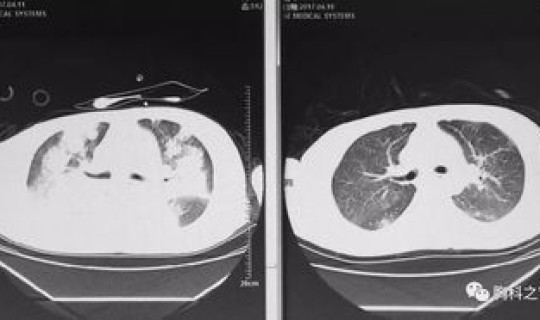

一、关于新型冠状病毒感染的肺炎,想知道的看过来 1、新型冠状病毒感染的肺炎临床表现有哪些?患者主要临床表现为发热、乏力,呼吸道症...